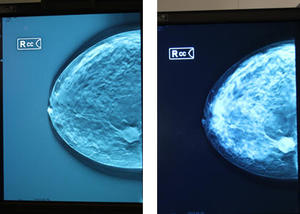

従来の2Dマンモ(右)とCTライク表示(左)の

AMULET Bellusは,大容量マンモグラフィデータの高速表示,ワンクリックでの画像比較表示,専用キーパッドやマウス操作時のアイコンの搭載など,シンプルなユーザーインターフェイス,富士フイルムの画像認識技術を生かした過去画像との高速切替表示(Intelligent Temporal Comparison:ITC),個々の乳房形状を反映したシェーマ作成機能など,多様かつ複雑なマンモグラフィ読影を支援する独自機能を多数搭載している。RSNA 2013の展示では,トモシンセシス画像の表示において,濃度表示を従来の2Dのマンモグラフィにあわせた画像に加えて,断層画像としてCTライク表示の要望が多かったことから,CT画像に近い表示モードの選択が可能になることを紹介した。